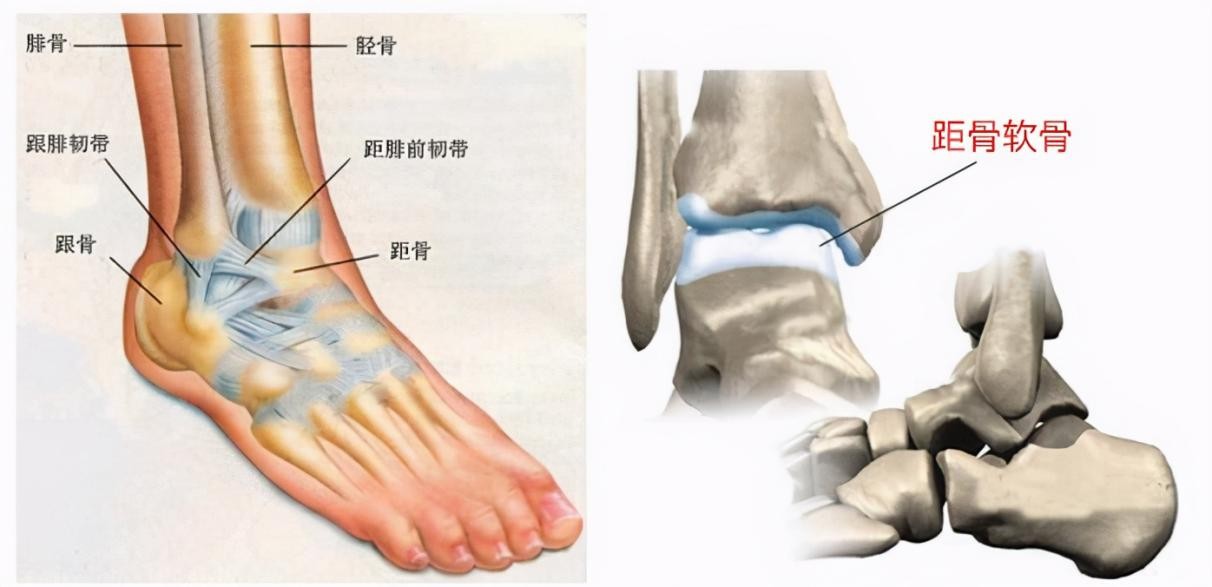

高清图解踝关节韧带解剖

图片尺寸660x495

值得收藏踝关节解剖分析高清图文详解

图片尺寸660x401